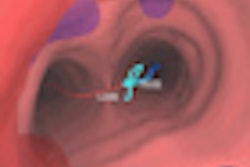

The Archimedes VBN System combines fused fluoroscopy, real-time bronchoscopy, and virtual bronchoscopic navigation for 3D views and access to nodules anywhere in the lung, with the ability to avoid major blood vessels through vessel mapping.